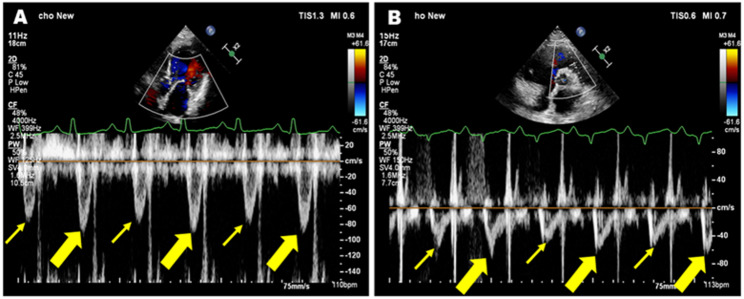

Background: Pulsus alternans (PA) is an intriguing phenomenon and a clinically rare entity. Accurately assessing cardiac function in patients with PA remains challenging. This study aims to investigate the myocardial mechanical characteristics and non-invasive hemodynamic profiles of PA patients using multiple echocardiographic imaging modalities.

Methods: Clinical and echocardiographic data were retrospectively analysed from 16 patients diagnosed with PA by echocardiography at our hospital between January 2021 and May 2025. In this study, the characteristics of PA were elaborated by multiple echocardiographic methods, and the non-invasive hemodynamic profile was determined by pulse-wave Doppler.

Results: Sixteen patients were enrolled. Seven were classified as NYHA class III and six as class IV. Elevated levels of NT-proBNP and hs-cTNT were observed in most patients. Follow-up ranged from 1 to 44 months, and five patients experienced adverse outcomes, including heart transplantation, rehospitalisation, and death. Within this cohort, three patients exhibited biventricular PA, while 13 patients presented with left ventricular (LV) PA. Key hemodynamic parameters varied significantly: LVOT-VTIstrong beat ranged from 11.3 cm to 29.2 cm, LVOT-VTIweak beat from 6.8 cm to 22.1 cm, and the variation rate between strong and weak beats (∆LVOT-VTI) ranged from 19 to 52%. Global longitudinal strain (GLS) was significantly reduced in 14 patients (range: - 1.2% to - 10.4%), while peak strain dispersion (PSD) increased (range: 47 ms to 117.5 ms). Two patients were excluded from strain analysis due to suboptimal imaging. Hemodynamic parameters (LVOT-VTIstrong beat, LVOT-VTIweak beat and ∆LVOT-VTI) showed strong correlations with GLS in PA patients (r = 0.806, P = 0.001; r = 0.642, P = 0.018 and r = 0.611, P = 0.027, respectively). NT-proBNP was significantly positively related to adverse outcomes in PA patients (r = 0.669, P = 0.012).

Conclusion: Echocardiography is essential for evaluating cardiac function in patients with PA. This study used multiple echocardiographic methods to delineate the characteristics of this intriguing clinical phenomenon. Non-invasive hemodynamic parameters are potentially important for prognosis assessment, and myocardial strain assessment provides valuable insights into myocardial mechanical features. A comprehensive analysis using multimodality imaging is crucial for accurately identifying this disease, potentially enhancing the understanding of the pathophysiological mechanism of PA.